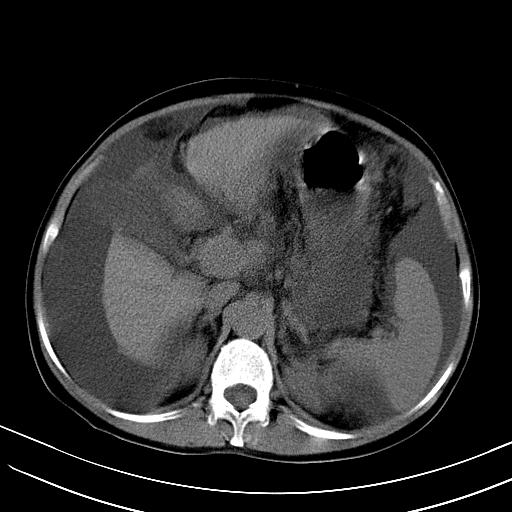

1)肝右叶肝癌并肝动静脉漏。2)肝硬化,腹水。3)胆囊炎。

肝右叶肝癌并动静脉漏,肝硬化,腹水。

右叶肝癌并肝动静脉漏(动脉期肝动脉及门静脉内均可见造影剂),肝硬化,腹水。(胆囊壁水肿)

1)肝右叶肝癌,考虑并发肝动静脉漏。扫描时间好像慢了。2)肝硬化,门脉高压、脾大、腹水。